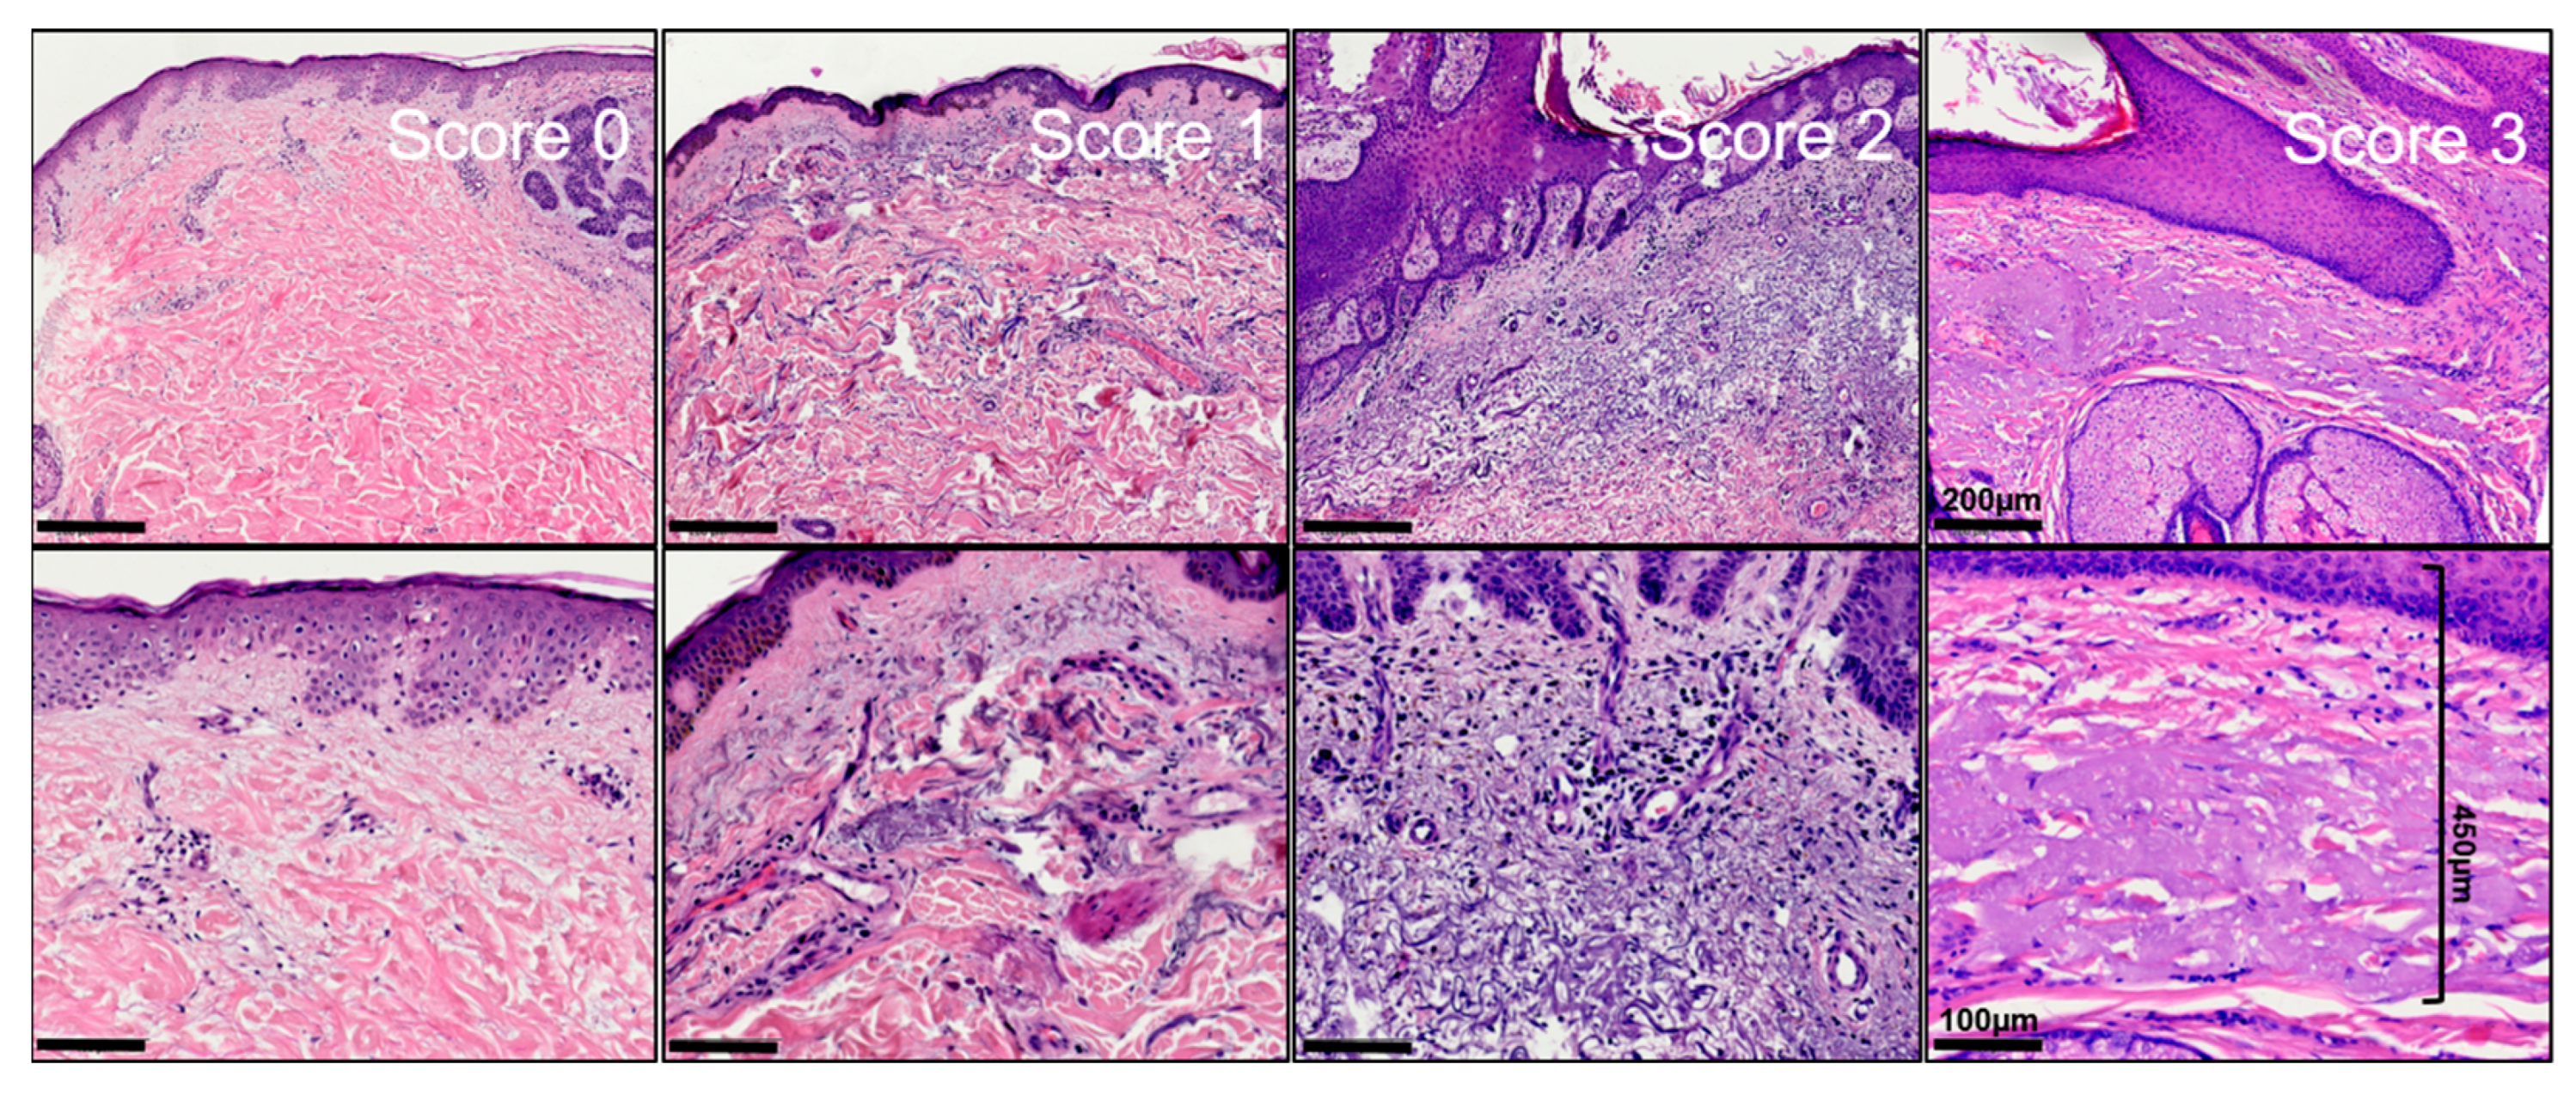

Figure 1.

Exemplified histopathological assessment measurement of actinic elastosis and scoring (tumor-associated elastosis grading—TEG). The thickness/width of elastotic material was measured in the vicinity of the tumor in absence of tumoral stroma. Elastosis was scored as follows: 0 = absent, 1 = low: Less elastotic material than regular fibers (collagenous and elastic), 2 = moderate: More elastotic fibers than regular fibers, 3 = strong: Complete or near complete loss of normal fibers/homogenous basophilic zone.

Sections were processed according to standard protocol and stained with hematoxylin–eosin. The histological examination was performed independently by two experienced dermatopathologists (K.D. and D.N.). Specimen slides were sorted by date of excision and not by tumor types to allow objective measurement. To assess the width of actinic elastosis, the widest identifiable elastotic fibre/area with basophilic degeneration in proximity of tumor and absence of tumoral stroma was measured orthogonally from the stratum granulosum using a scale ocular. To assess the degree of actinic elastosis, a semiquantitative score was established as follows: (0 = absent, 1 = low: less elastotic material than regular fibers (collagenous and elastic), 2 = moderate: more elastotic fibers than regular fibers, 3 = strong: complete or near complete loss of normal fibers/homogenous basophilic zone). If their counts were consistent within a range of 1 point in the score and a range of 20% in measurement of the width of elastosis, the mean was calculated and used for subsequent analyses. The agreement between both raters was medium for the degree of AE (kappa = 0.334; 95%-CI: 0.27, 0.40) as well as for TEG (ICC = 0.463; 95%-CI: 0, 0.72), indicating that the mean of two raters is a good choice to obtain reliable values. Inconsistent results could be resolved using a discussion microscope. The width was multiplied with the semiquantitative score resulting in the newly defined tumor-associated elastosis grading score (TEG). Curettage material, punch biopsies and specimens without normal tissue in the vicinity were excluded from further analysis to allow sufficiently reliable results. In the end, a total of n = 328 specimen from n = 321 patients were included in the statistical analysis.